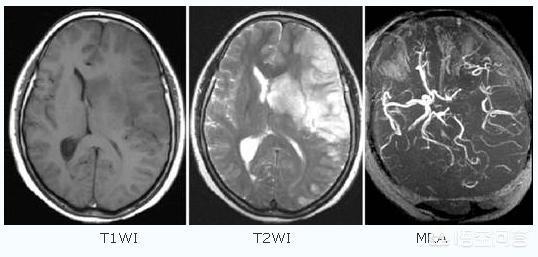

L'infarctus cérébral, également connu sous le nom clinique d'accident vasculaire cérébral ischémique, est un problème d'approvisionnement en sang des vaisseaux sanguins du cerveau causé par un certain nombre de raisons telles que l'athérosclérose, l'hypertension, le diabète sucré et les maladies coronariennes, entraînant une ischémie, une hypoxie et une nécrose des tissus cérébraux locaux.

Les accidents vasculaires cérébraux peuvent être divisés en deux catégories : les accidents hémorragiques cérébraux et les accidents ischémiques cérébraux. L'accident vasculaire cérébral ischémique (infarctus cérébral) est le type d'accident vasculaire cérébral le plus courant en Chine.L'accident vasculaire cérébral ischémique est un état dans lequel le flux sanguin vers le cerveau est insuffisant en raison de l'obstruction des vaisseaux sanguins, ce qui entraîne une nécrose ischémique et une perte de fonction des tissus cérébraux, l'embolie cérébrale et la thrombose cérébrale étant les causes les plus courantes. Avant l'apparition de l'AVC ischémique, les patients peuvent présenter des symptômes temporaires d'ischémie cérébrale (communément appelés mini-AVC), notamment l'apparition soudaine d'un engourdissement et d'une faiblesse unilatérale des bras et des jambes, des troubles de l'élocution, une vision floue, une perte d'équilibre, etc.Il s'agit d'un précurseur important de l'accident vasculaire cérébral... Les plaques d'athérome et la sténose des artères carotides cérébrales sont des facteurs importants de l'accident vasculaire cérébral ischémique.Outre les personnes d'âge moyen et les personnes âgées, les patients souffrant d'hypertension artérielle, d'hypercholestérolémie, de diabète sucré et les fumeurs de longue date constituent également les groupes les plus fréquents.

- Thrombose cérébrale :(1) Formation de caillots sanguins en raison de l'augmentation de la viscosité du sang. (2) Obstruction de la circulation sanguine due à l'accumulation de graisse dans les artères du cerveau, qui forme une plaque et aggrave le rétrécissement des vaisseaux sanguins dans le cerveau.

- embolie cérébraleLes obstructions provenant d'autres parties du corps que le cerveau, telles que les caillots sanguins, la graisse, les bulles d'air, etc., pénètrent dans les vaisseaux sanguins cérébraux via le système circulatoire et provoquent une perturbation localisée de la circulation sanguine cérébrale.